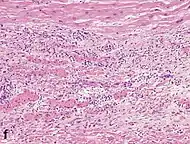

Differential diagnoses for myocardial fibrosis:

- Interstitial fibrosis, which is nonspecific, having been described in congestive heart failure, hypertension, and normal aging.[25]

- Subepicardial fibrosis, which is associated with non-infarction diagnoses such as myocarditis[26] and non-ischemic cardiomyopathy.[27]

Healthy myocardium versus interstitial fibrosis in dilated cardiomyopathy. Alcian blue stain.

Healthy myocardium versus interstitial fibrosis in dilated cardiomyopathy. Alcian blue stain. Subepicardial fibrosis (epicardium at top)

Subepicardial fibrosis (epicardium at top)